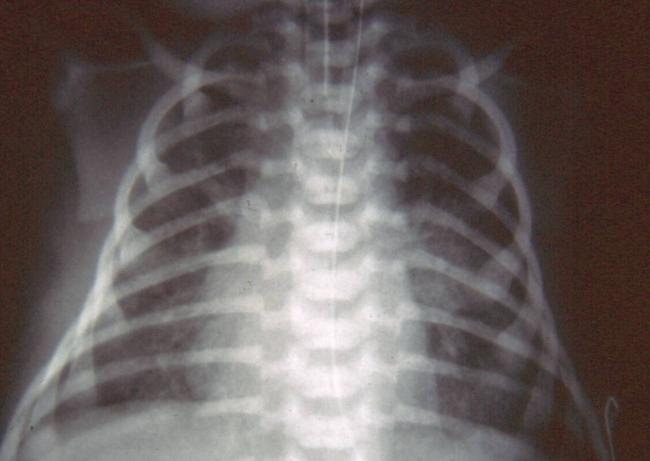

Самым результативным способом выявления болезни легких, является прослушивание новорожденного на присутствие хрипов в области грудной клетки и рентгеновское исследование.

Диагностика пневмонии у новорожденных проводиться с помощью рентгенологических и лабораторных исследований. Кроме того, верная постановка диагноза невозможна без учета клинических симптомов и данных анамнеза. Если у крохи выявлено воспаление легких, нужна госпитализация.

- Сегментарная – данный вид воспаления развивается после ОРВИ или другой вирусной инфекции. Выявить его можно только с помощью рентгеновского снимка, так как симптоматика очень незаметная и поставить диагноз на ее основании невозможно. Выздоровление, как правило, наступает на третью неделю после начала лечения.